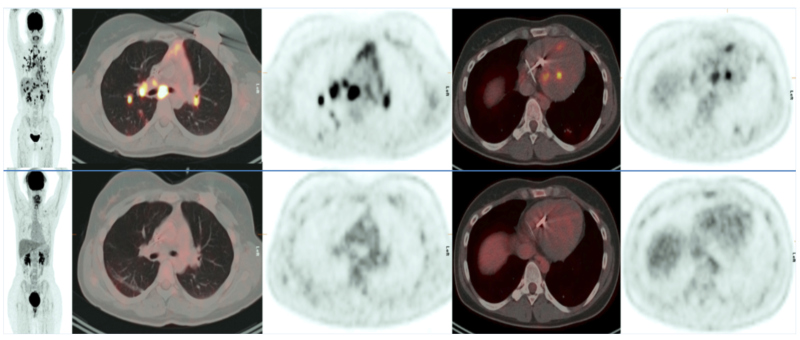

Mujer de 34 años, diagnosticada en octubre de 2017 como portadora de sarcoidosis estadio 2, con repercusión sistémica bajo forma de cardiosarcoidosis con afectación del sistema de conducción. Inicia tratamiento con glucocorticoides y ciclofosfamida, pero se evidencia la enzima convertidora de angiotensina (ECA) en franco ascenso, por lo que en diciembre de 2018 se solicita un estudio de 18F-FDG PET/TC para evaluar respuesta al tratamiento y datos de actividad inflamatoria actual. El estudio muestra afectación linfática supra e infradiafragmática, hepática, esplénica, pulmonar, ósea y cardíaca (Fig. 1, fila superior). Se realiza una biopsia con resección atípica de lóbulo superior e inferior pulmonar derecho, con resultado anatomopatológico de inflamación granulomatosa no necrotizante de tipo sarcoideo con fibrosis peribronquiolar, septal y subpleural, corroborando el diagnóstico clínico. Se inicia en marzo de 2019 tratamiento con metotrexato, solicitándose un estudio de control con 18F-FDG PET/TC para valorar respuesta. El nuevo estudio muestra una respuesta metabólica completa al tratamiento (Fig. 1, fila inferior).